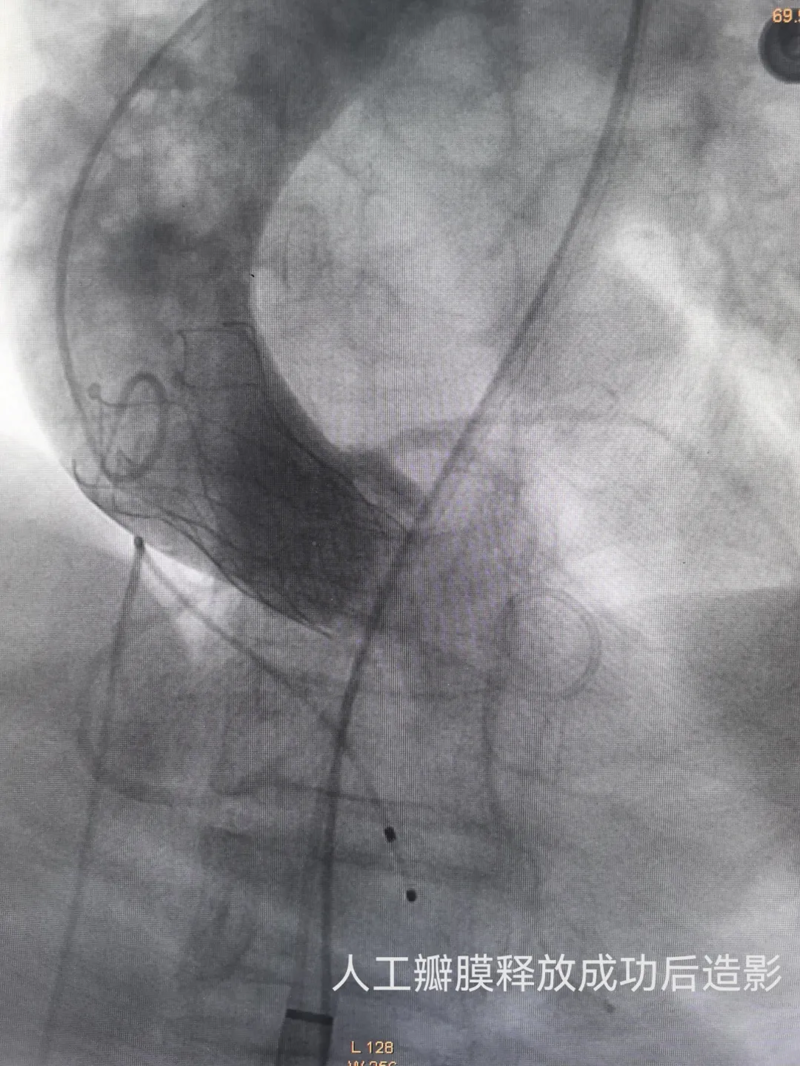

手术当日,在中山大学第一附属医院广西医院袁军教授的指导下,河池市第三人民医院心血管内科手术团队通过股动脉穿刺建立微创通路,将人工瓣膜精准送达患者病变主动脉瓣位置,在临时起搏器保护及实时造影监测下完成瓣膜释放。整个手术历时仅1小时余,术中患者生命体征平稳,几乎无明显出血。术后复查显示,人工瓣膜启闭功能良好,平均跨瓣压差降至15mmHg,术后症状明显好转。

术前术后